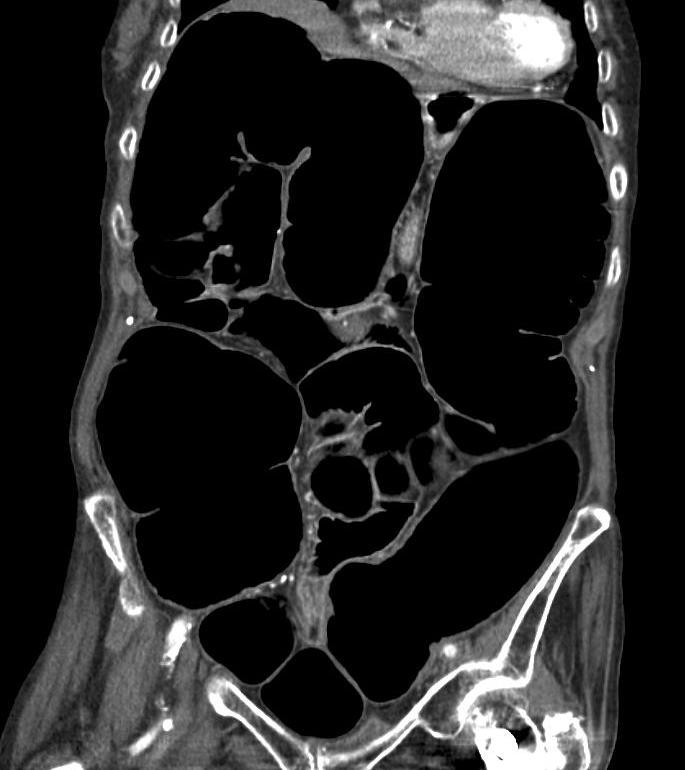

가성 장폐색 증후군은 임상적 양상에 따라 급성 또는 만성으로 분류된다. 급성 대장 가성 장폐색(ACPO; Acute Colonic Pseudo-Obstruction)은 때때로 오길비 증후군이라고도 불리며, 대장이 심하게 확장되는 특징을 보인다. 적절한 감압 조치가 이루어지지 않으면 장 천공, 복막염 및 사망에 이를 수 있는 위험이 있다. 만성 장 가성 폐쇄(Chronic Intestinal Pseudo-Obstruction)는 이름 그대로 만성적인 경과를 보이는 질환이다.[24]